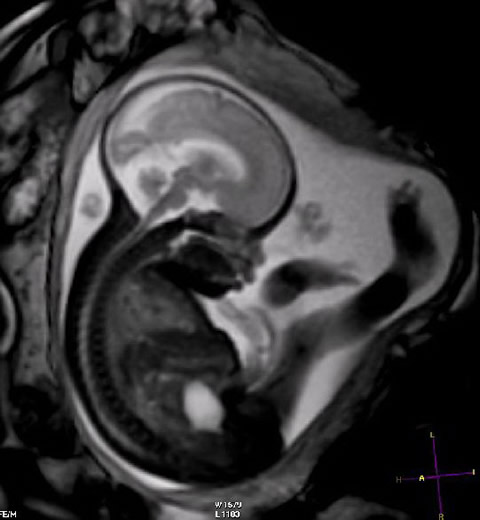

Utilidad de la exploración mediante resonancia magnética cerebral en los pacientes con un diagnóstico de migraña que insisten realizar en el estudio

17 noviembre 2017

Am J Med, 13 de noviembre de 2017 La resonancia magnética (RM) cerebral obtenida a petición específica del paciente con diagnóstico de migraña en presencia de un examen neurológico normal tiene un rendimiento equivalente al de la población general asintomática. Los pacientes no parecen tener más información que el clínico examinador con respecto a la detección de anomalías estructurales subyacentes, y la RM cerebral no debe realizarse como parte de la evaluación de rutina de la migraña sin una indicación clínica clara.